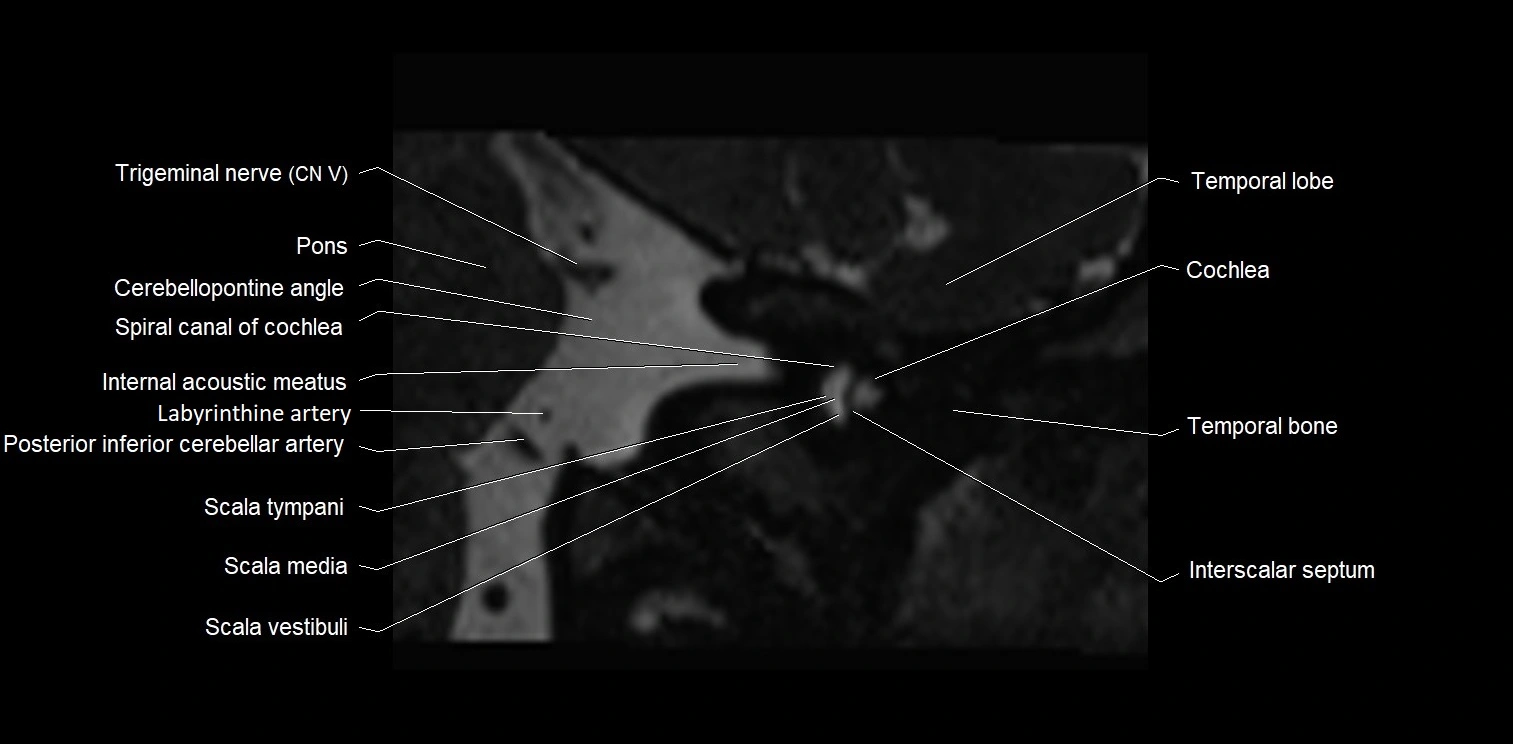

MRI images

image